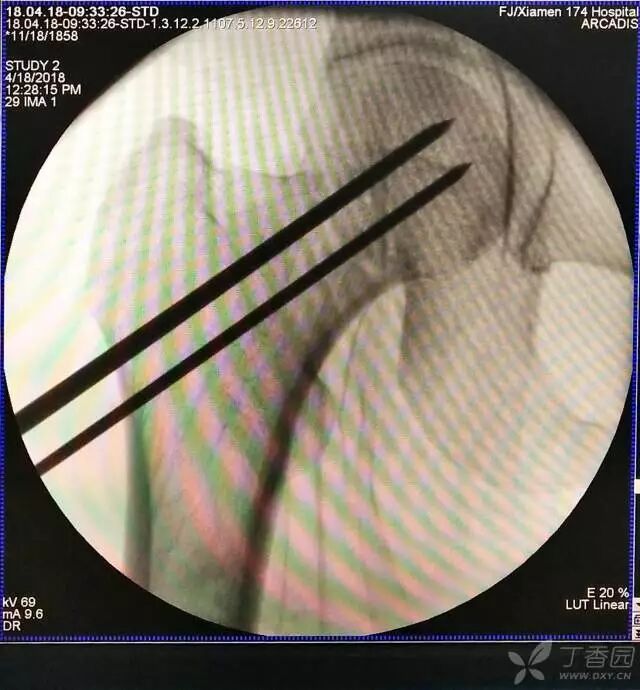

5. 打入第一枚倒品字下方导针,跟体外导针基本重叠

牵引床怎么用视频详解:如何不使用牵引床做好一台股骨颈骨折?_https://www.jmylbn.com_新闻资讯_第13张

6. 然后依次打入倒品字上方的两枚导针